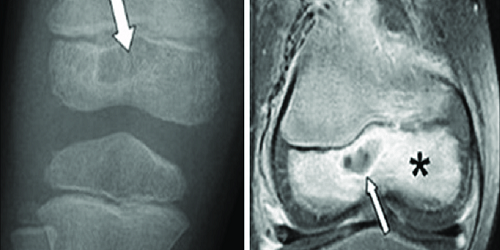

Apselerin Oluşması: Osteomiyelit tedavi edilmezse, kemik içinde apselerin oluşma riski artar. Apseler, enfeksiyonun birikmesi ve sıvı dolu boşlukların oluşmasıyla karakterizedir. Bu apselerin tedavisi genellikle cerrahi müdahale gerektirir ve enfeksiyonun yayılmasını önlemek için önemlidir.